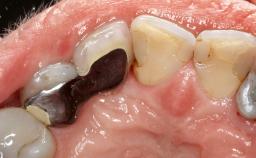

Paolo Casentini and Matteo Chiapasco present a case in which the peri-implant defect was not suitable for a fully regenerative approach. It involves implant removal, use of a CAD/CAM customized titanium mesh in the grafting phase, and placement of new implants. A 62-year-old woman was referred for consultation regarding her implant-supported prosthesis replacing teeth 14 to 16. The patient’s main concern was pain and recurrent swelling in the right posterior maxilla. The patient also reported difficulty and discomfort when brushing the area. The patient reported she had been treated in another country, where she had received three implants in combination with sinus-floor augmentation for the replacement of the posterior maxillary teeth three years earlier. The patient indicated “endodontic complications” to be the reason for the extraction of the teeth.